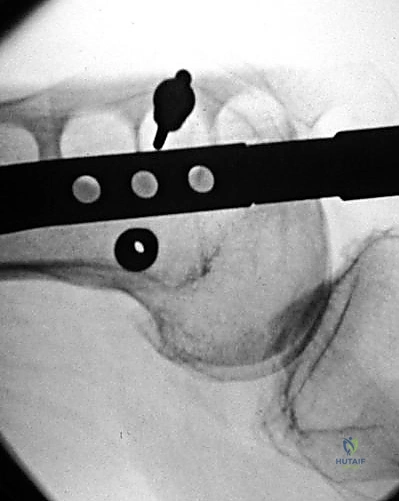

من الناحية الإشعاعية (باستخدام جهاز الأشعة السينية داخل غرفة العمليات - Fluoroscopy)، يحرص الأستاذ الدكتور محمد هطيف على تحديد هذه النقطة بدقة بالغة. في المنظر الأمامي الخلفي (AP)، تقع النقطة في خط الوسط تماماً بين اللقمتين. أما في المنظر الجانبي (Lateral)، فتكون أمام "خط بلومنسات" (Blumensaat's Line) مباشرةً.

صورة شعاعية توضح كسراً حاداً في عظم الفخذ ناتجاً عن صدمة عالية الطاقة، مما يستدعي تدخلاً جراحياً فورياً.

التشخيص الدقيق بالأشعة السينية يحدد نوع الكسر وموقعه، وهو الخطوة الأولى في وضع خطة العلاج الجراحي.